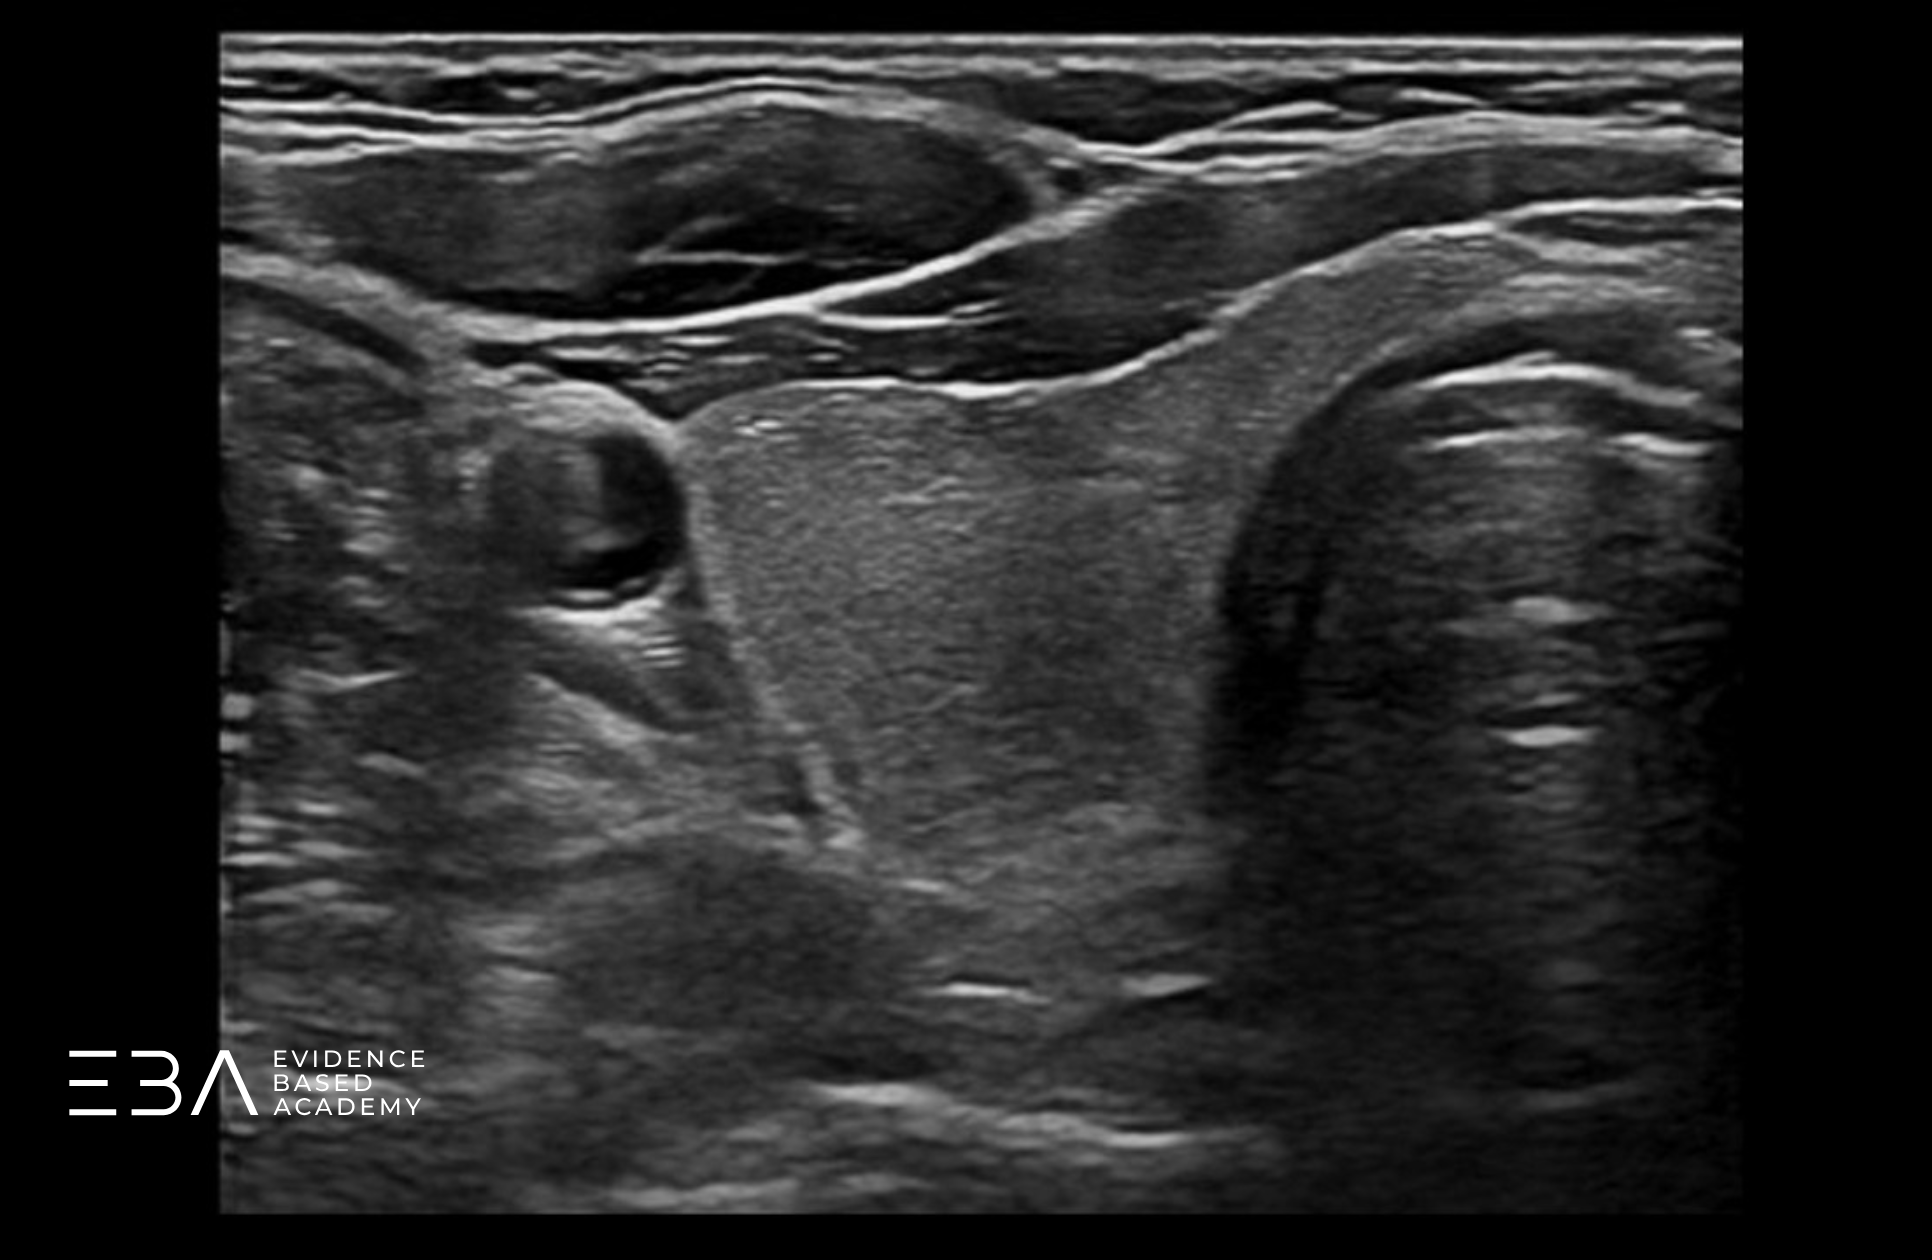

Poza znajomością prawidłowej anatomii tarczycy ważna jest również wiedza na temat jej otoczenia. Na poniższym schemacie oznaczyliśmy struktury sąsiadujące z tarczycą.

Schemat prawego płata z podpisami otaczających struktur.

Warto zwrócić uwagę na strukturę położoną grzbietowo do tarczycy, zwykle po lewej stronie szyi. Przełyk, bo o nim mowa, w projekcji poprzecznej może początkowo imitować zmianę ogniskową. Zmiana projekcji na podłużną pozwala uwidocznić jego charakterystyczny kształt i rozwiać wątpliwości.